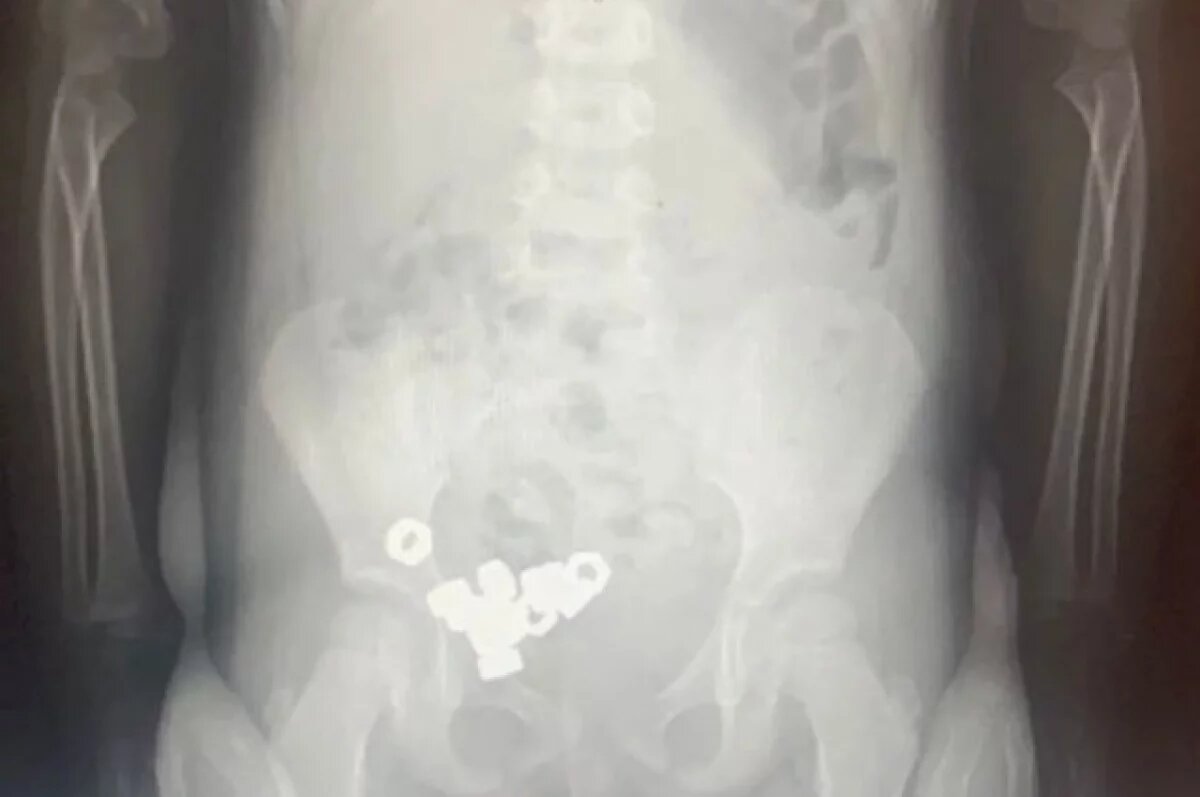

16 гаек проглотил трёхлетний ребёнок в Воронеже. Его доставили в областную детскую клиническую больницу №2. Об этом сообщили в региональном минздраве в понедельник, 17 ноября.

При осмотре юного пациента врачи не выявили у него симптомов проглатывания инородных тел. Однако рентген брюшной полости показал наличие в желудочно-кишечном тракте ребёнка маленьких гаек.

Малыша госпитализировали. Поскольку гайки были не инертными и не магнитными, врачи выбрали консервативное лечение. Они назначили пациенту диету, покой и контроль стула. Кроме того, медики проводили ему рентгенографию в динамике.

К третьему дню все инородные тела вышли естественным путём. Ребёнка уже выписали из больницы.